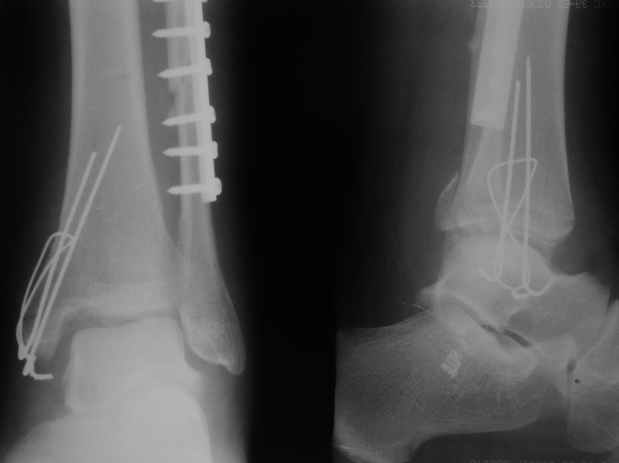

>На сделанных у нас снимках видно, что не все благополучно...

Неравномерность суставной щели может быть связана с разрывом глубокой порции дельтовидной связки и ротацией м/берцовой кости за счет поврежденных структур синдесмоза(репозиция ее на уровне перелома как-будто удовлетворительная).

Мы бы, сблизив берцовые кости чрескожно наложенным репозиционным зажимом, провели позиционный межберцовый винт чуть ниже пластинки в положениий максимального тального сгибания стопы и ... на следующий день разрешили бы полностью наступать без гипса, брейса и т.п., но в обуви с небольшим каблуком 2-3 см и супинатором. Через месяц-полтора -винт удалить (если конечно не сломается).

По моему мнению,ассиметрия суставной щели обусловлена импрессией медиальной части суставной поверхности б/б кости. Да, позиционный винт здесь не лишен, но через 4 недели целесообразность его проведения сомнительна, брейс, ограничение осевой нагрузки достаточно.Есть еще деонтологические аспекты повторной операции, не все так плохо выполнено предыдущим доктором!

Выполнено действительно неплохо, только позиционный винт забыли провести.

Вот и я тоже так думаю.

Перелом типа Вебер С с эверсионным механизмом травмы всегда сопровождается повреждением дистального межберцового синдезмоза, поэтому вместе с фиксацией переломов лодыжек( малоберцовой кости) автоматом выполняется фиксация синдесмоза винтом, который обычно удаляется через 8 недель -

Расширенная медиальная щель более чем на 4 мм и укорочение малоберцовой более чем 2 мм, а перелом заднего края большеберцовой смещения более 2мм с вовлечением 30% поверхности сустава, считается отходом от нормы голеностопного сустава, и подлежит к оперативному вмещательству.

С мнением «провести позиционный межберцовый винт чуть ниже пластинки в положениий тыльного сгибания стопы» согласен, но я бы нагрузку начал через три недели и удаление шурупа можно провести через 6-8 недель.

Для облегчения удаления сломанных шурупов (случается часто) рекомендую фиксацию двумя 3.5мм кортикальными шурупами на 3 мм длиннее, тот же сломанный шуруп легко удаляется с медиальной стороны.

Меньше всего волнует положение медиальной лодыжки - в любое время можно провести остео или реостеосинтез, при несращении можно просто резецировать без ущерба для движений в голеностопе. Здесь обошлись фиксацией одним 4 мм канюлированным шурупом.